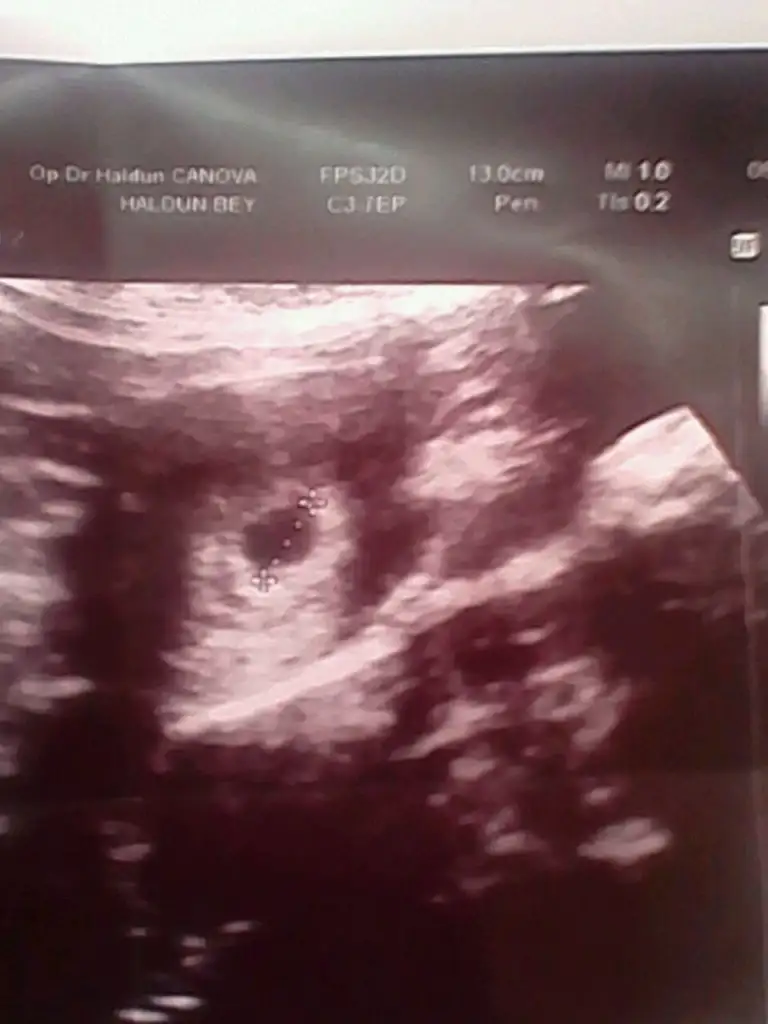

Var cnm hemen hemen herkesin ayni gibi eklemeye calsiirimarkadaslar lütfen bi bakin. benim bu ultrason fotom 5+5 . doktor birsey demedi gerci bebek ve kalp atisini haftaya görebiliriz dedi sadece yolk kesesini görmüstük ama bana normal gebelik kesesi kücük geldi. sizce nasil elinde böyle fotosu olan var mi baska

Benimkinde 13mm yaziyor usttekesen 5 mm canım

kesen 5 mm canımm

Benimkinde 13mm yaziyor ustte